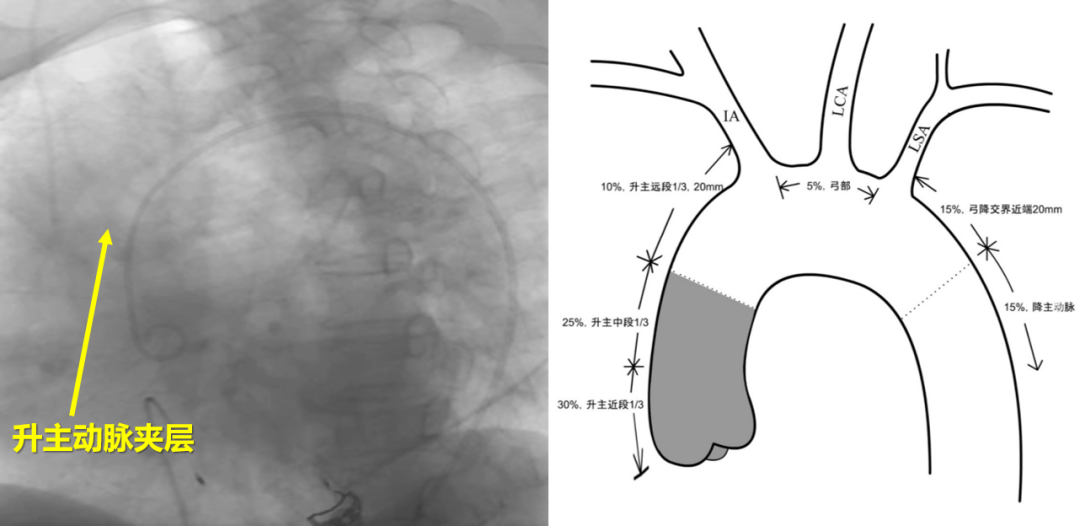

升主动脉夹层在主动脉夹层中约占70%。长期以来,这一区域的腔内治疗被认为是介入治疗的“禁区”,原因显而易见:

升主动脉解剖结构特殊——口径大、距离短、缺乏足够锚定区、非直筒结构、小弯侧短,同时还面临着脑梗、逆行A型夹层(RTAD)、瓣膜损伤等高风险。加上缺乏专用器具,过去只能依靠“off-label”支架移植物进行探索性治疗。

然而,随着定位-后释放技术的持续改进、杂交手术室的广泛建立、TAVR治疗经验的爆发式积累、新型弓部重建器具的出现,以及影像融合辅助技术的发展,升主动脉夹层微创腔内治疗的壁垒正在被逐一攻克。

锚定区策略:锚定区的选择需根据病变类型个体化处理。对于夹层病变,锚定区需求相对较短;而对于动脉瘤性病变,则需更长锚定区。

支架放大率控制在10%-30%的宽泛范围